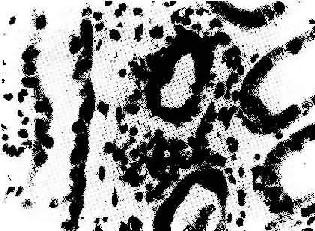

(1)细胞型排斥反应:常发生在移植后几个月,临床上表现为骤然发生的移植肾功能衰竭。镜下可见肾间质明显水肿伴有大量细胞浸润,以单核细胞和淋巴细胞为主,并夹杂一些具有嗜酸性胞浆和水泡状胞核的转化淋巴细胞和浆细胞。免疫组化染色证实有大量CD4+、CD8+细胞存在。肾小球及肾小管周围毛细血管中有大量单核细胞,间质中浸润的淋巴细胞可侵袭肾小管壁,引起局部肾小管坏死(图4-4)。

肾移植急性排斥反应

图4-4 肾移植急性排斥反应

肾间质水肿,肾小管上皮细胞变性,间质及毛细血管内有大量单核细胞